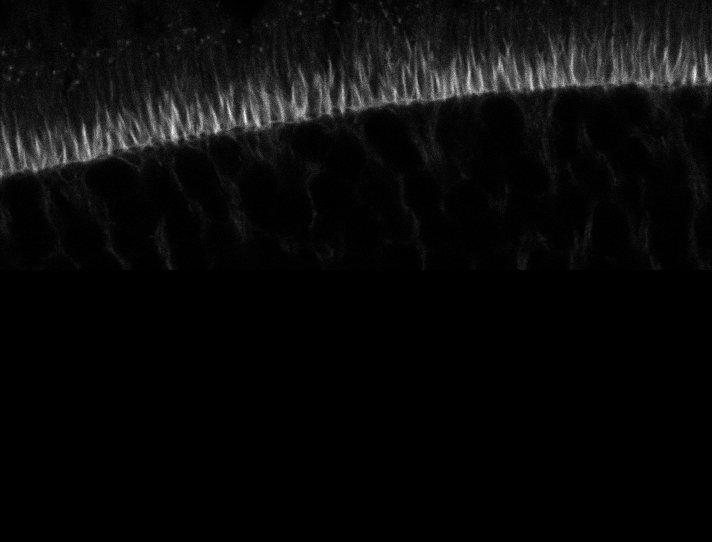

Healthy Retina

Unhealthy Retina

Actin